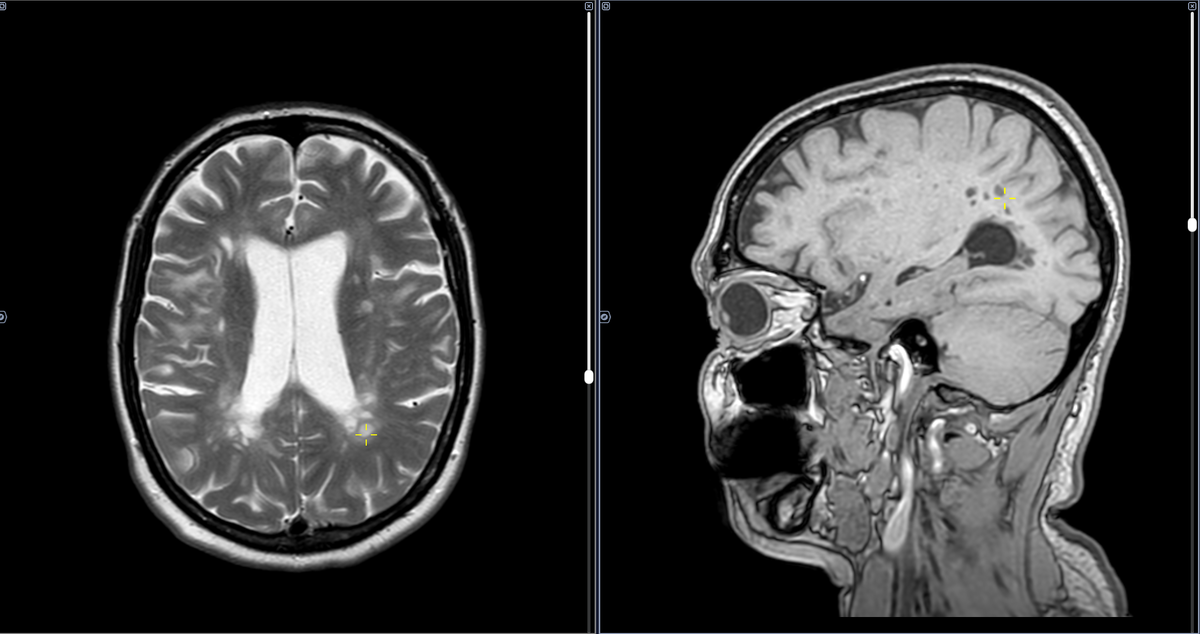

Рассеянный склероз – это хроническое аутоиммунное заболевание центральной нервной системы, при котором иммунная система ошибочно атакует миелиновую оболочку нервных волокон, вызывая воспаление и повреждение. В белом веществе полушарий головного мозга выявляются множественные очаги высокого МР- сигнала в Т2- ви и FLAIR, изо-, гипоинтенсивные в Т1, размерами до 7х7 мм. Большинство очагов паравентрикулярной локализации имеет продолговатую форму, ориентированы перпендикулярно оси мозолистого тела, отдельные расположены юкста- субкортикально, имеют округлую и неправильную форму, часть очагов в перивентрикулярных отделах со склонностью к слиянию. ОБЩЕЕ КОЛИЧЕСТВО ГИПЕРИНТЕНСИВНЫХ ОЧАГОВ В РЕЖИМАХ Т2-ВИ И Т2-FLAIR: - Юкстакортикальные/кортикальные очаги Т2: до 8 штук. - Перивентрикулярные очаги Т2: более 10 штук. - Инфрантенториальные очаги Т2: 2 очага. ОБЩЕЕ КОЛИЧЕСТВО ОЧАГОВ, НАКАПЛИВАЮЩИХ КОНТРАСТНОЕ ВЕЩЕСТВО В РЕЖИМЕ Т1-ВИ GD+: - Перивентрикулярные очаги Gd+: 1 очаг. Критерии пересмотра

В белом веществе полушарий головного мозга выявляются множественные очаги высокого МР- сигнала в Т2- ви и FLAIR, изо-, гипоинтенсивные в Т1, размерами до 7х7 мм.

Большинство очагов паравентрикулярной локализации имеет продолговатую форму, ориентированы перпендикулярно оси мозолистого тела, отдельные расположены юкста- субкортикально, имеют округлую и неправильную форму, часть очагов в перивентрикулярных отделах со склонностью к слиянию.

ОБЩЕЕ КОЛИЧЕСТВО ГИПЕРИНТЕНСИВНЫХ ОЧАГОВ В РЕЖИМАХ Т2-ВИ И Т2-FLAIR:

- Юкстакортикальные/кортикальные очаги Т2: до 8 штук.

- Перивентрикулярные очаги Т2: более 10 штук.

- Инфрантенториальные очаги Т2: 2 очага.

ОБЩЕЕ КОЛИЧЕСТВО ОЧАГОВ, НАКАПЛИВАЮЩИХ КОНТРАСТНОЕ ВЕЩЕСТВО В РЕЖИМЕ Т1-ВИ GD+:

- Перивентрикулярные очаги Gd+: 1 очаг.

Критерии пересмотра MакДональда 2017 соблюдены:

1. Диссеминация в пространстве : >1 Т2 гиперинтенсивного очага > 3 мм по длинной оси - да

Перивентрикулярно: 1 и более очагов - да

Юкста--субкортикально: 1 и более очаг - нет

Инфратенториально: 1 и более очаг - да

Заключение:МР - признаки очаговых изменений головного мозга демиелинизирующего характера с признаками активности процесса.